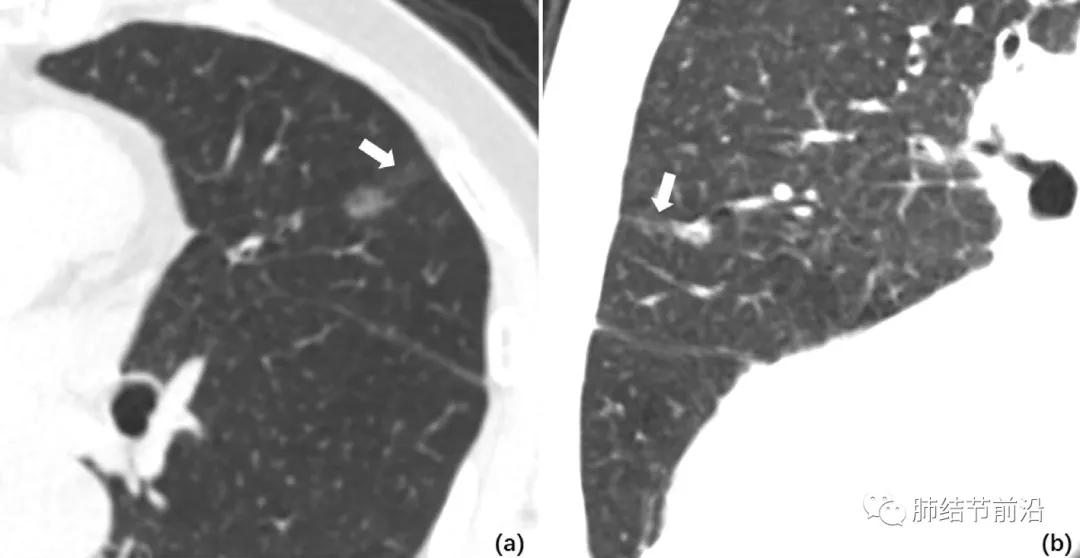

STAS显示为肺结节非常规的相邻双中心生长

如果有影像上怀疑STAS,建议早期切除。但是磨玻璃结节患者也不必紧张,对于贴壁样的磨玻璃结节,极少会有STAS出现。